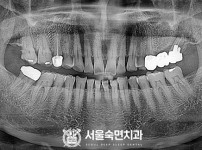

임플란트-전후사진3

치과를-선택할-때-꼭-확인하세요-서울숙면치과-임플란트-전후사진